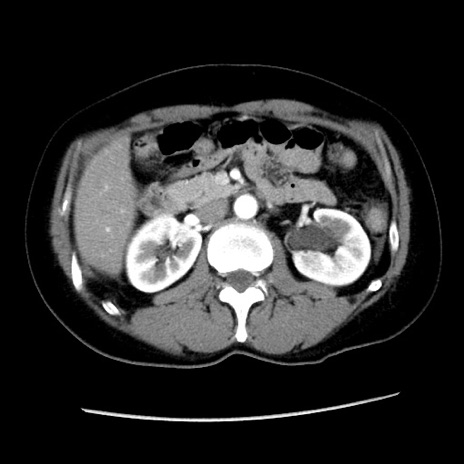

症例10(横断像)

【症例】 50歳代女性

【主訴】 腹痛

【現病歴】前日生レバーを食べた。今朝に排便あり。 昼前に突然発症の腹痛を生じ、当院救急外来を受診した。

【既往歴】 子宮筋腫にてで子宮全摘後

【身体所見】 意識清明、腹部:平坦、軟、下腹部やや左を中心に圧痛・反跳痛あり、筋性防御あり

【データ】WBC 7800、CRP 0.07